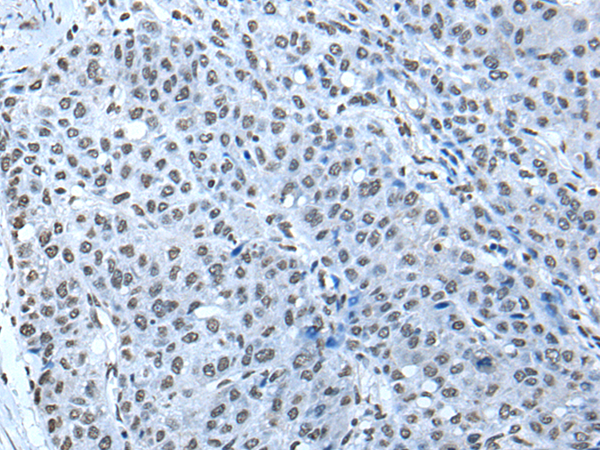

分类: 科研抗体货号: P12835别名: ZNF923应用: IHC反应种属: Human